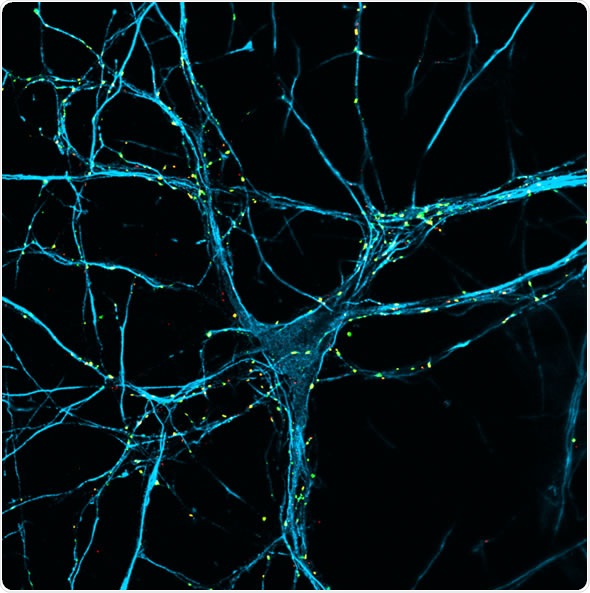

Image credit: Dr Galli / Parkinson’s UK

Synapses are the sites that connect neurons – sites where information is passed from one neuron to another. They are highly specialized structures and synaptic function is crucial for normal brain function.

There are over a hundred billion synapses in the brain. Importantly, there is a loss of synapses in the early stages of neurodegenerative diseases and we suspect that this is what causes symptoms to appear.

We know a lot about the formation of synapses and how the synaptic terminal of one neuron passes information to the receiving terminal of another neuron. We know which proteins are present and which ones act as the sensors of the molecule that will transmit information.

We know how the molecules are sending information, whether it be glutamate for excitatory synapses, dopamine for modulatory synapses or GABA for inhibitory synapses, for example. We know there is a variety of synapses that will either increase or stop the signal passing from one neuron to another.